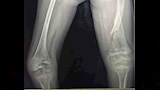

نجح فريق طبي بمستشفى سوهاج العام، في إجراء جراحة عظام كبرى لطفلة تبلغ من العمر 6 سنوات، مصابة بمرض العظام الزجاجية وكسر في عظمة الفخذ، وهي من العمليات الدقيقة والمعقدة؛ نظرًا لهشاشة العظام الشديدة التي يسببها المرض.

واستغرقت العملية نحو 3 ساعات، تضمنت إصلاح التشوهات بعظمة الفخذ وتثبيت الكسر باستخدام مسمار نخاعي متمدد ذاتي الإطالة، المخصص لحالات العظام الزجاجية.